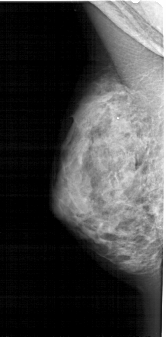

A_1660_1.RIGHT_MLO

RIGHT_MLO LINES 5446 PIXELS_PER_LINE 2431 BITS_PER_PIXEL 12 RESOLUTION 43.5 OVERLAY

FILE: A_1660_1.RIGHT_MLO.OVERLAY

TOTAL_ABNORMALITIES 1

ABNORMALITY 1

LESION_TYPE CALCIFICATION TYPE PUNCTATE DISTRIBUTION SEGMENTAL

ASSESSMENT 4

SUBTLETY 1

PATHOLOGY BENIGN

TOTAL_OUTLINES 1